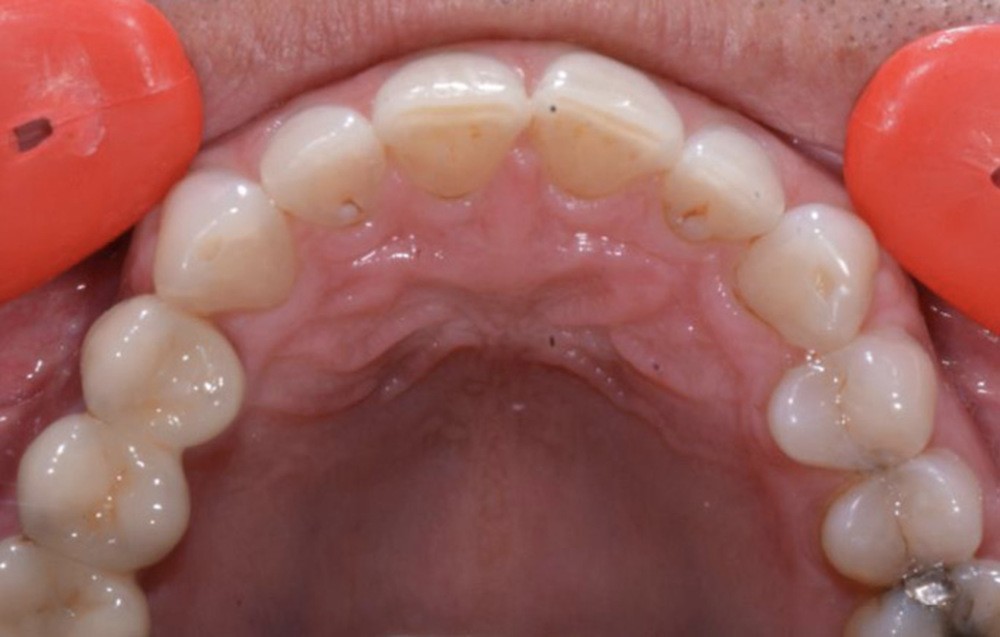

Présentation du cas clinique (fig. 1 à 3)

Le patient, âgé de 58 ans, présente un encombrement dentaire mandibulaire de 5 mm dans un contexte squelettique hypodivergent.

À la radiographie panoramique, on constate une lésion apicale sur 15 et une atteinte inter radiculaire sur 16 ainsi qu’une légère rotation de 21 sans gêne pour le patient.